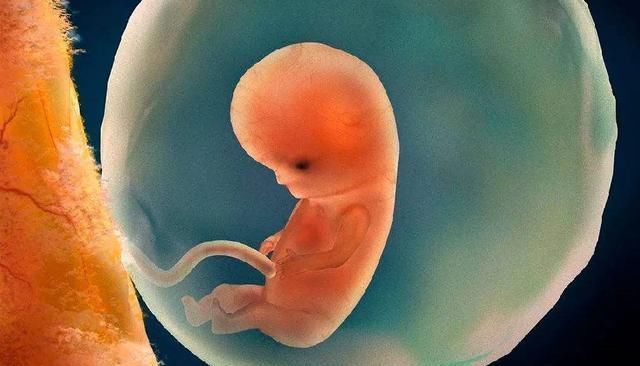

怀孕的过程虽然很漫长,但被很多人看作是很幸福的时光,慢慢感受着一个小生命在自己的身体中成长给人带来满足感,可是你真的知道宝宝在你腹中是如何成长的吗?想不想知道现在他是什么样子的呢?

生命的源头来自于精子和卵子结合成的受精卵。女性会大概在经前14天排卵,如果这段时间精子能够进入输卵管腔的话,24h之内受精卵就可以形成,受精后大概一周的时间受精卵就能在子宫内膜着床。

医生会从准妈妈的末次月经开始算妊娠期,会比受精卵形成的时间早2周,从这个时候开始算整个妊娠的过程,共40周。

妊娠4周时,孕妇的子宫还没有发生明显的变化,胎儿目前还是胚胎,已经有胎盘和体蒂了;

妊娠8周时,准妈妈应该已经可以感受到早孕反应了,胎儿也已成胎形,头部、身体、四肢都能看得出来,心脏和大脑也已经开始发育;

妊娠12周时,各位准妈妈大多发现自己变胖了吧,不仅重量增加,连腰围也增加了,此时胎儿已经具备人形,很多器官已开始工作和发育;

16周时,肚子是不是已经鼓起了呢,乳房也会变涨,而胎儿身长大约16cm,肺部开始工作了,四肢已经发育完成,可以做出不少动作了因此准妈妈也可以感受到胎动;

20周时,这段时间大家应该是比较轻松的,吃的不少,也不容易恶心,行动也比较方便,胎儿也长到了25厘米左右,开始出现体脂,也开始生长毛发,并且他的感官也开始飞速发育;

24周时,由于腹部愈发鼓了,孕妇的体态也和之前有了很大差别,行动时重心会向后移动,此时的胎儿身长大概30厘米,大脑也在迅速发育,脂肪开始变厚,不过皮肤仍旧是薄薄的,而细小支气管和肺泡也在慢慢发育。

28周时,已经进入孕晚期了,准妈妈们也会感受到腰酸背痛,而宝宝发育到了大概35厘米,也正在努力沉积脂肪和进行呼吸运动,他的眼睛也能够闭合、睁开了。

32周时,准妈妈这这段时间运动也开始变得迟缓,能感受到背部、大腿的疼痛,要注意休息,胎儿看起来也很像刚出生的宝宝了,各器官发育接近成熟。

36周时,准妈妈的体重目前已是巅峰,腹部非常大有很沉重,肚脐也是外凸的样子,能感受到腹部下坠感,这周结束宝宝就能称为足月儿了。

40周时,准妈妈要随时准备生产了,此刻宝宝已经发育成熟,身长大约50厘米,生存能力也比较强了。

以上就是胎儿在孕妈肚子里的发育过程,你都清楚了吗?